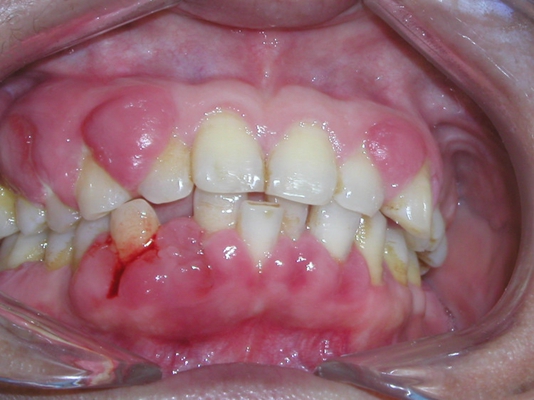

牙周炎圖片

牙周袋 (8)